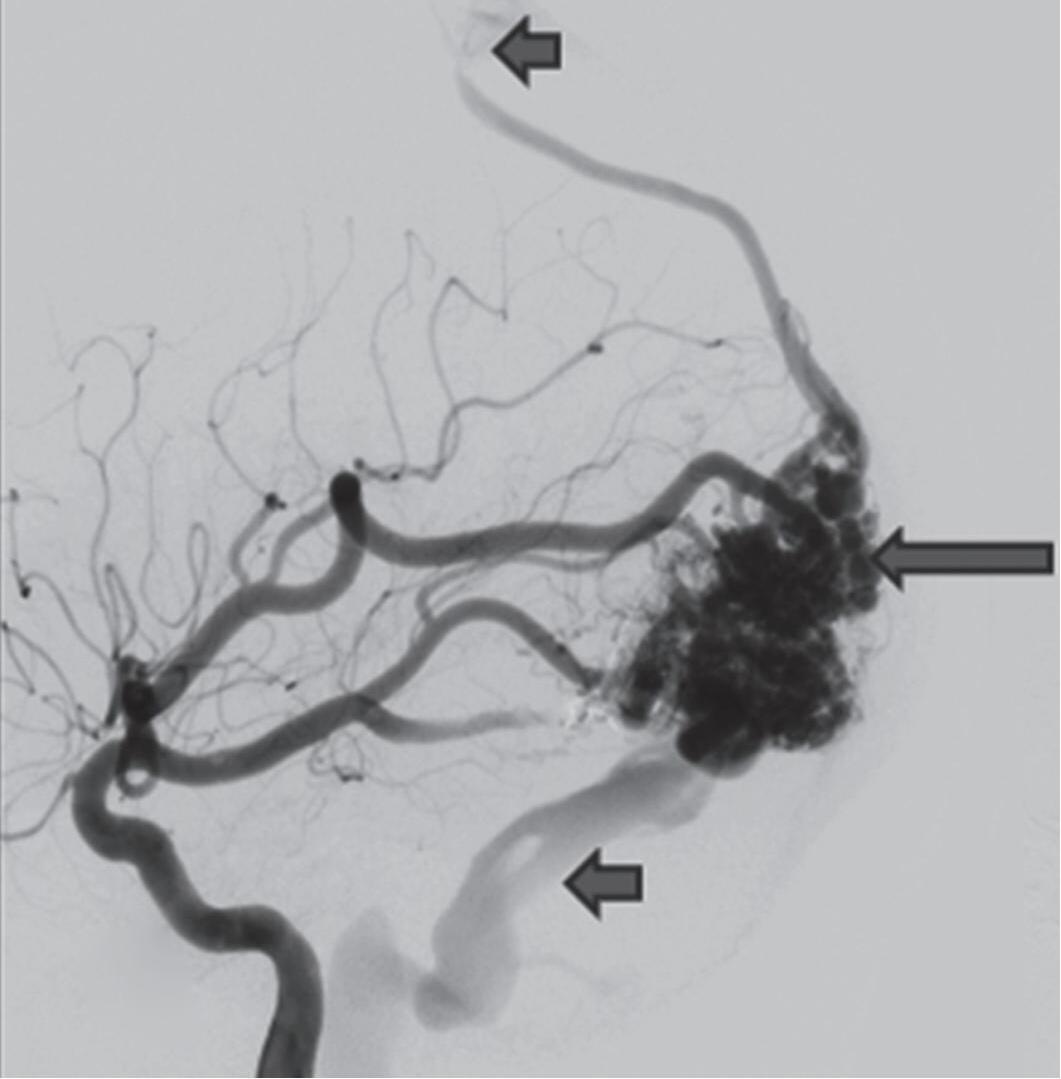

Fig. 1-8. (a-c) RNM T1 com contraste, cortes sagital (a), coronal (b) e axial (c) demonstrando MAV não rota com nidus localizado no lobo occipital à esquerda (setas longas). (d) Arteriografia digital cerebral com injeção de contraste via carótida direita (AP) mostrando a contribuição da carótida direita na irrigação da MAV contralateral. (e,f) Com injeção de contraste via carótida esquerda, em Perfil e AP respectivamente, observa-se nidus compacto nutrido por ramos da artéria cerebral média à esquerda e a veia de drenagem precoce se dirigindo para o seio sagital superior. Projeções em AP (g) e em perfil (h) demonstrando a contribuição do sistema vertebrobasilar por meio de ramos distais da artéria cerebral posterior à esquerda e drenagem para os seios sagital superior e sigmoide à esquerda (setas curtas).